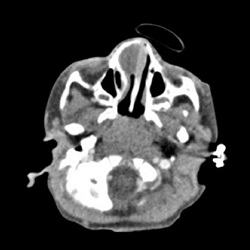

#AJNRcc >> November 20, 2025 >> What is the diagnosis for this 22-year-old woman with an insidious onset of diplopia, left ophthalmoparesis, trismus, and a history of root canal treatment with persistent left facial pain for 2 years. Submit your answer at https://t.co/L2j0hK0RCd.